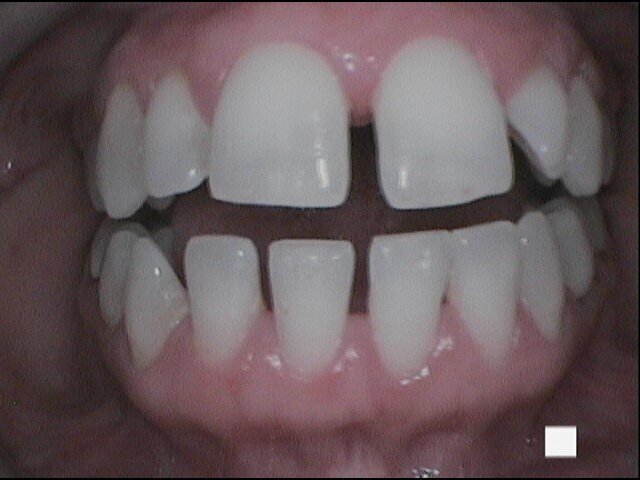

Si presenta alla nostra attenzione un giovane paziente di anni 26, non fumatore, in apparente salute sistemica, in terapia ortodontica con mascherina invisibile lamentando un cattivo odore dell’allineatore, percepito in maniera fastidiosa grazie all’utilizzo obbligato della mascherina per le norme di sicurezza anti-Covid 19. Invitiamo il paziente a rimuovere le mascherine al fine di eseguire un esame obiettivo intra-orale e valutare le condizioni di integrità degli allineatori.

Il paziente ha un buon controllo del biofilm batterico. Viene consigliato il controllo dell’alito attraverso il test organolettico sniff test e il paziente si rassicura poiché non avverte cattivo odore. Chiediamo al paziente in che modo igienizza invece il dispositivo ortodontico e ricordiamo al paziente di aver consigliato l’utilizzo della compressa igienizzante. Il paziente ci riferisce di non aver usato la pastiglia poiché divide l’abitazione con suoi colleghi universitari e non ha piacere di immergere il dispositivo in un bicchiere d’acqua con l’aggiunta della pastiglia igienizzante, poiché lo trova sconveniente e se ne vergogna. Il paziente chiede se può disinfettarla facendola bollire (Figg. 1-9).